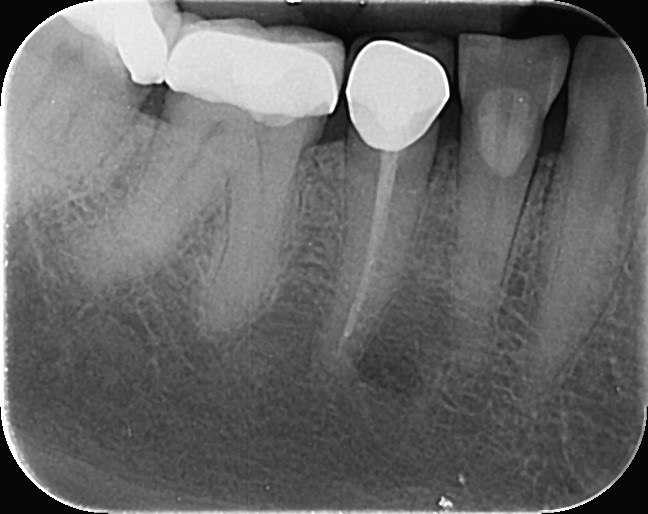

1. Which surfaces shows dental caries?

2. Which surface needs restoration?

3. What is the caries level on the distal surface of the tooth # 3.6?

4. Which surface needs restoration?